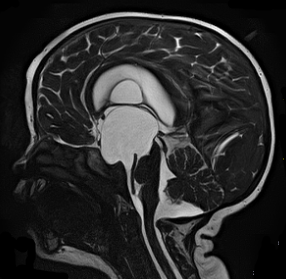

МРТ снимки мальформации Денди-Уокера